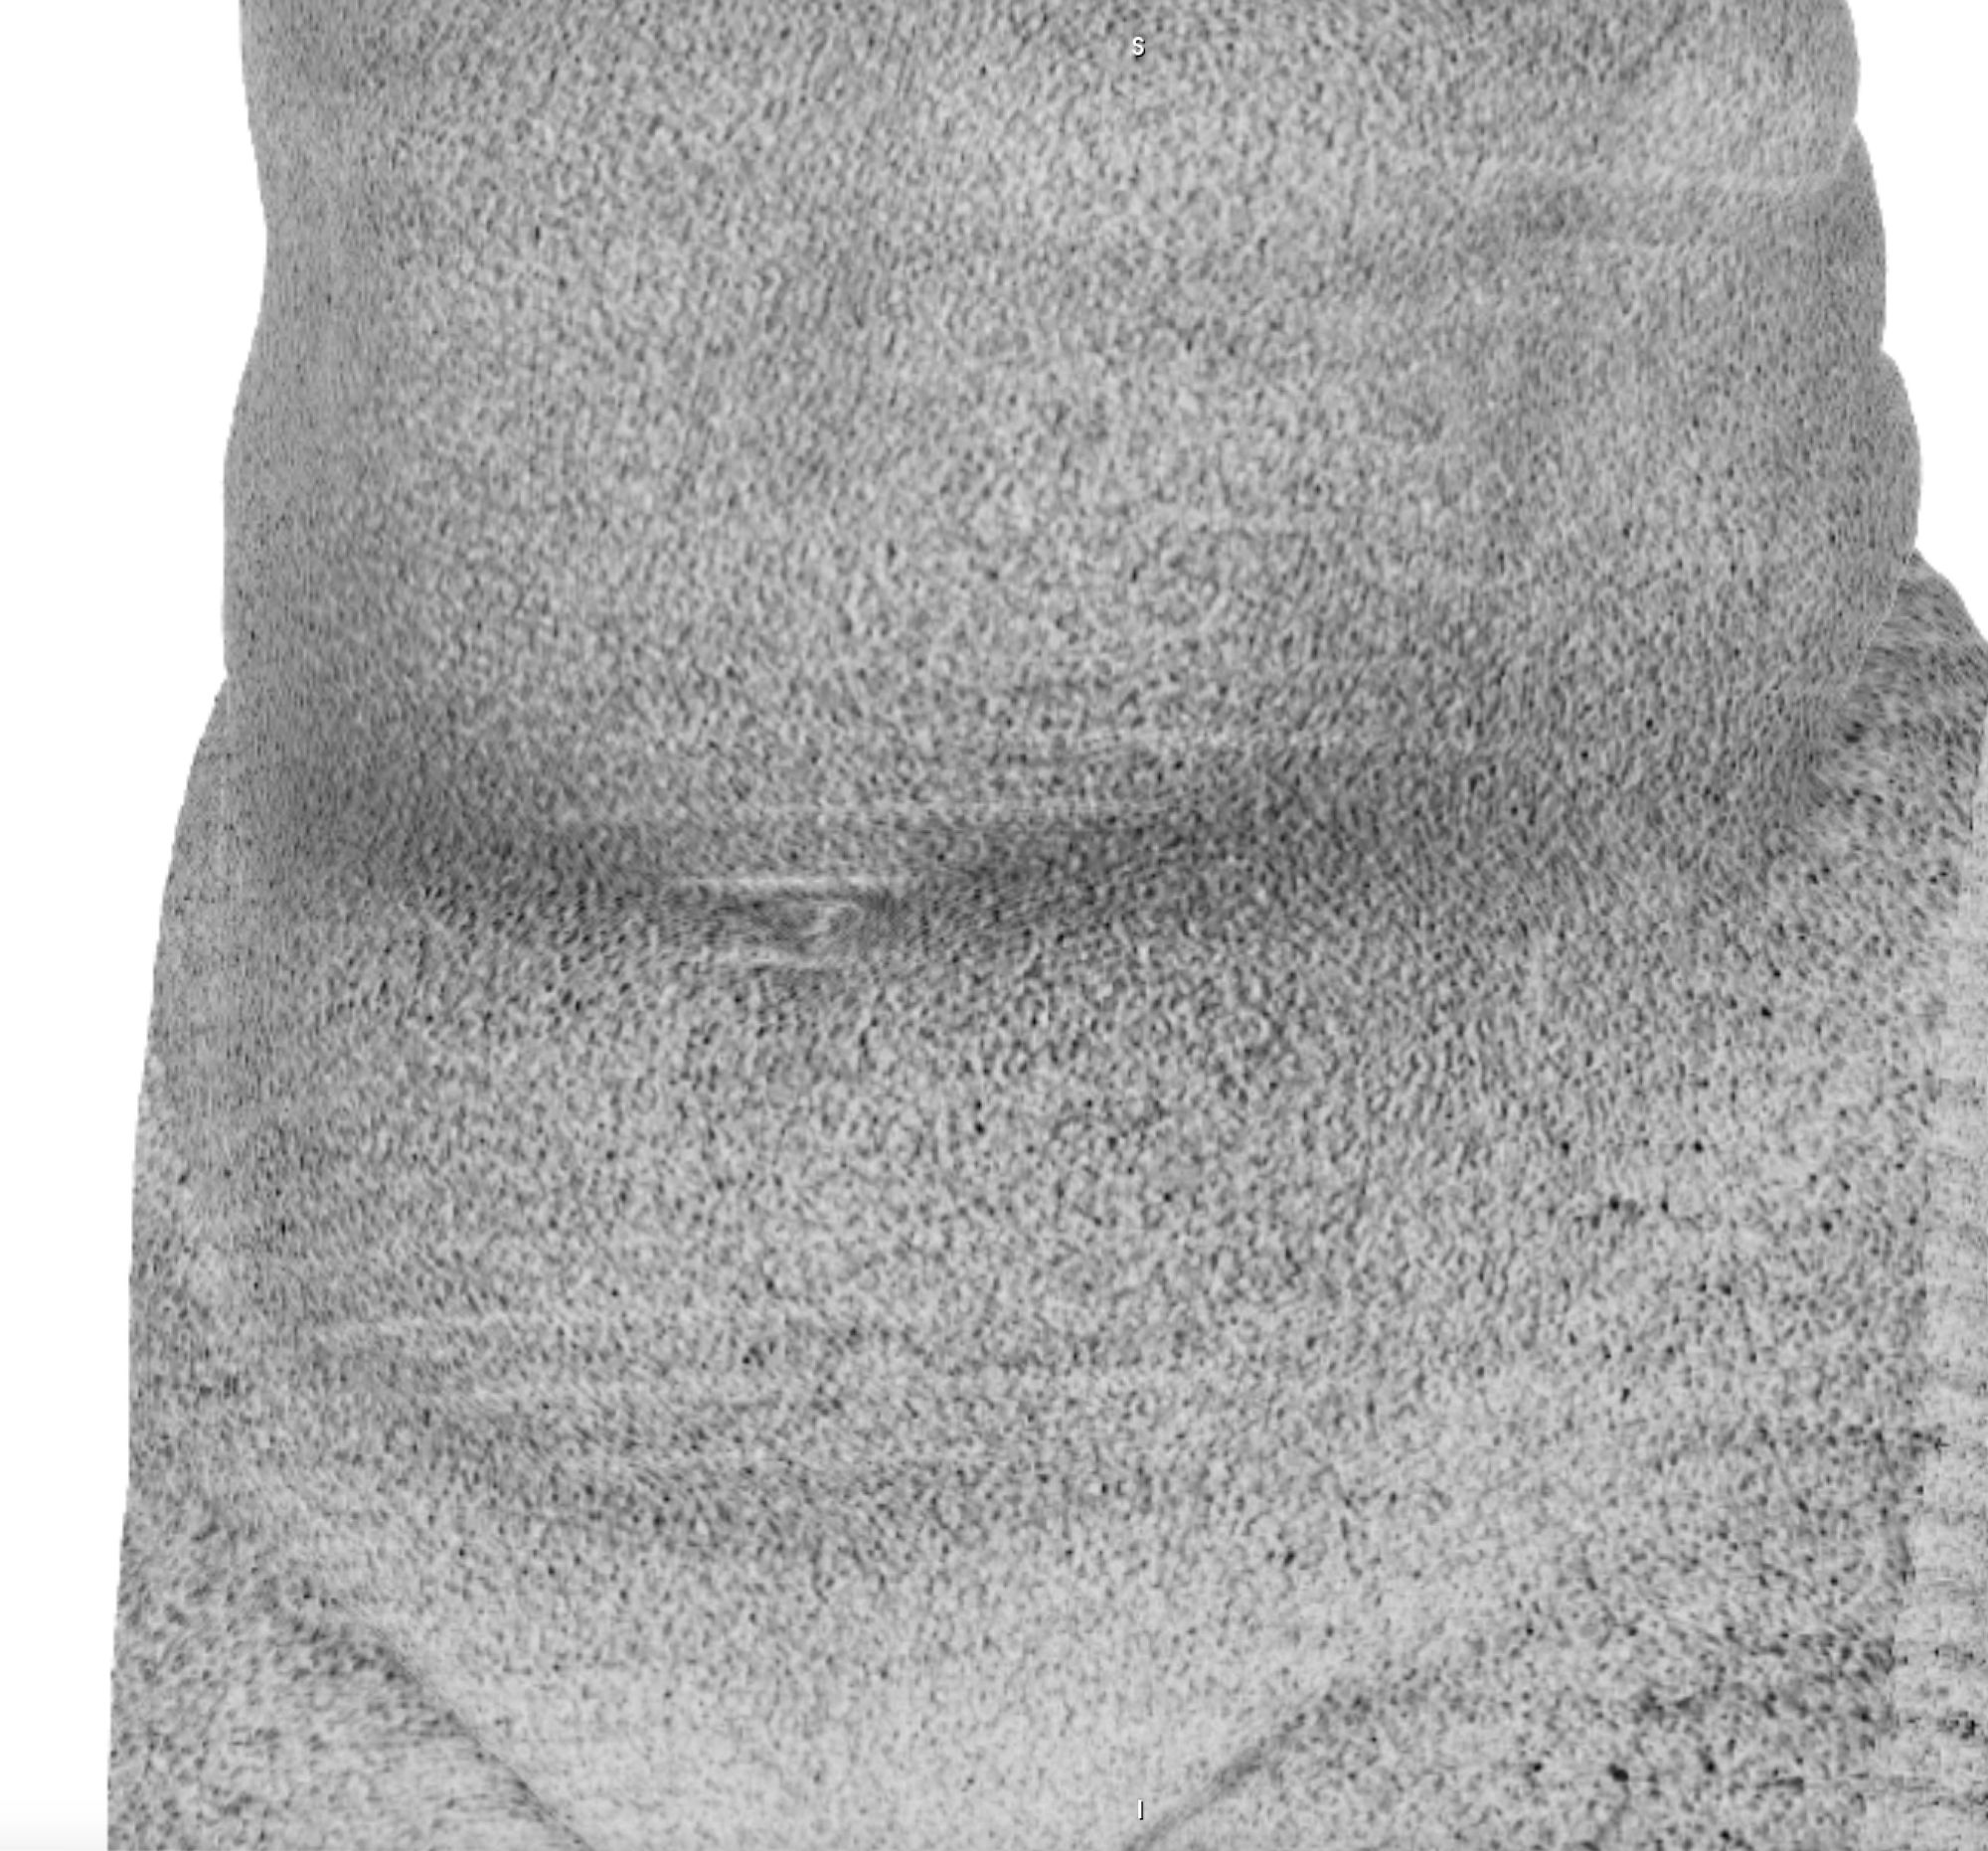

Chasing Intensities considers the body through its relationship to contemporary medical imaging technologies.

In this project, I look at the visual limit between the inside and the outside, the inner and the outer. I combine different visual approaches to materialise the body, using medical imagery, photography from manuals and radiology software. Decontextualised from their origin, these images speak of medicine’s relationship to both sex and violence, and remind us that, in medicine, to go into the body is always to go into the image first.